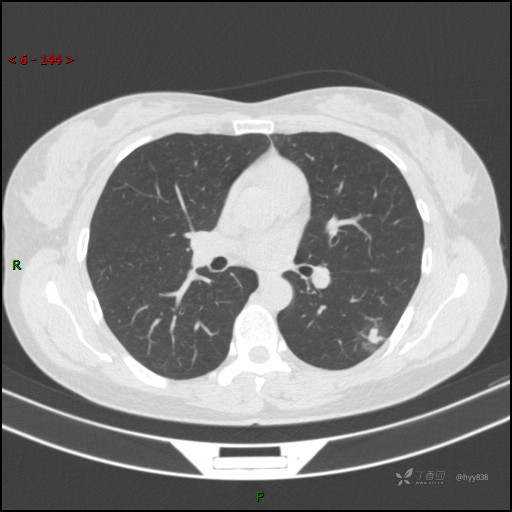

胸膜下“煎鸡蛋征”,感染 VS 炎症 VS 肿瘤,挑战有你---结果公布~

患者性别:女

患者年龄:46岁

简要病史:干咳半月伴左胸部不适

辅助检查:CT

临床诊断:结节

讨论:病变性质?